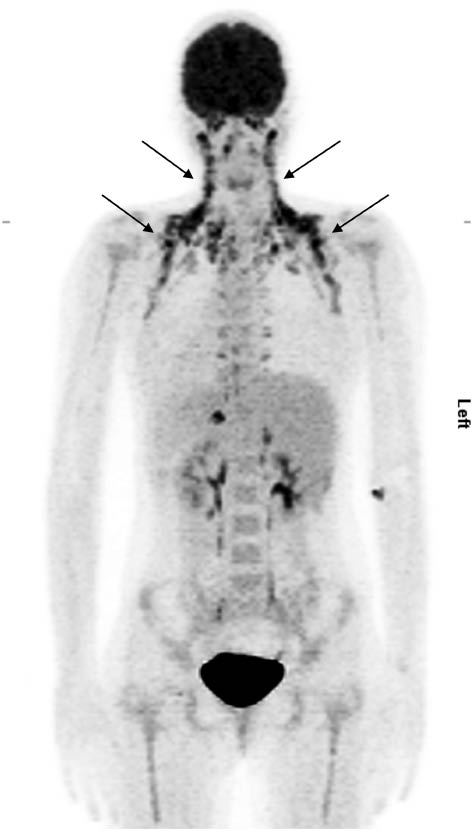

While BAT has long been appreciated as an important player in cold defense in human infants, BAT thermogenesis was thought to be completely blunted during adulthood. This view changed in 2009 when three groups reported independently that active BAT was present in adults and could be activated via cold exposure [16, 18, 20]. Only moderate cold stimulation (14–17°C) for a short period of time (1–2 h) is sufficient to augment glucose uptake in BAT accompanied by enhanced fatty acid oxidation and increased energy expenditure [22, 137, 138]. The observations that BAT activity is negatively associated with human obesity and type 2 diabetes have further propelled clinical research in this field [16, 17, 20, 22, 25–27]. FDG-PET/CT is currently considered the gold standard for measuring BAT activity in humans, which correlates positively with intracellular glucose uptake. However, other techniques including magnetic resonance imaging (MRI) are being investigated as alternative approaches for BAT detection [16, 17, 71, 137, 139–142]. Using FDG-PET/CT scans a typical anatomical pattern of BAT distribution has been identified in humans. Most active BAT is located in the cervical, parasternal, para- and pre-vertebral region [16, 18, 20, 70], (Figure 2). Reports that short-term cold exposure can trigger glucose uptake in distinct fat depots provided the first evidence that thermogenically-active BAT pre-exists in adult humans and that the observed cold-mediated alterations are not dependent on de novo brown fat formation. However, several case studies suggest that the recruitment of brown adipocytes into white fat depots can occur in humans like in rodents. In patients with untreated pheochromocytoma, significant amounts of active brown/beige adipocytes have been found in visceral adipose tissue, which is most likely due to a chronic overstimulation with catecholamines [143, 144]. A few months after resection of the tumor, FDG positivity of the visceral fat depot was no longer present, consistent with a regression of thermogenically-active brown/beige fat [144]. Some controversy exists regarding the molecular signature of human BAT, with reports demonstrating a gene expression pattern that resembles the classic interscapular brown fat in mice, while others argue that human BAT also displays characteristics of inducible beige fat cells [14, 15, 70–72, 145]. Nonetheless, all authors agree that the promotion of BAT activity drives energy expenditure in humans and thus may counteract obesity. Despite such evidence, recent attempts to harness BAT thermogenesis therapeutically have had little success. Administration of ß-adrenergic compounds such as ephedrine or isoproterenol has only shown modest effects on glucose uptake in BAT as determined by FDG-PET scans [144, 146–149]. Irrespectively, the use of such substances is of very limited therapeutic value, given their known side effects on the cardiovascular system. In contrast, moderate cold exposure (17°C) for 6 weeks, 2 h daily significantly enhanced BAT activity and energy expenditure accompanied by a decrease in body fat mass [22]. Nonetheless, effective pharmacological approaches to counteract obesity are still lacking, therefore the search for novel therapeutic strategies targeting brown fat continues.

Active brown adipose tissue visualized by 18fluor-deoxy-glucose positron emission tomography coupled with computed tomography (arrows). Provided by the Division of Nuclear Medicine, Department of Radiology and Nuclear Medicine, Medical University of Vienna.